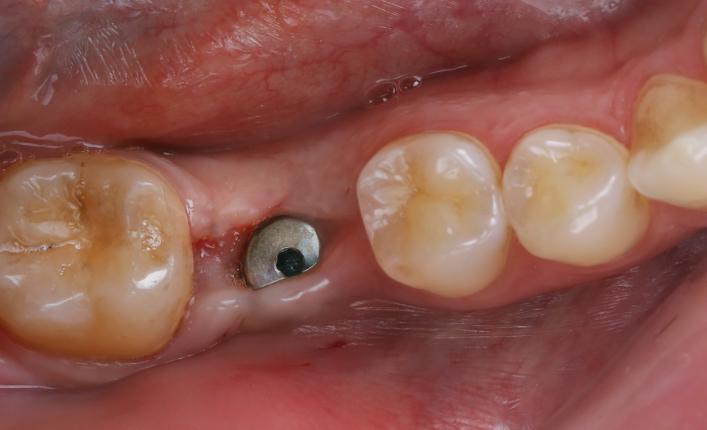

三个月到半年后,你回来了,那颗钛螺丝钉经过漫长的沉睡之后已经和你的骨头完全长在了一起。这在生物学上叫“骨结合”,然后就可以进行二期手术了。

这次很简单,只需再开一个小小的口子,把之前埋进去的螺丝头露出来,装上一个叫“愈合基台”的金属帽。它的作用是把牙龈撑开一个圆形的坑,为了将来装牙冠做准备。